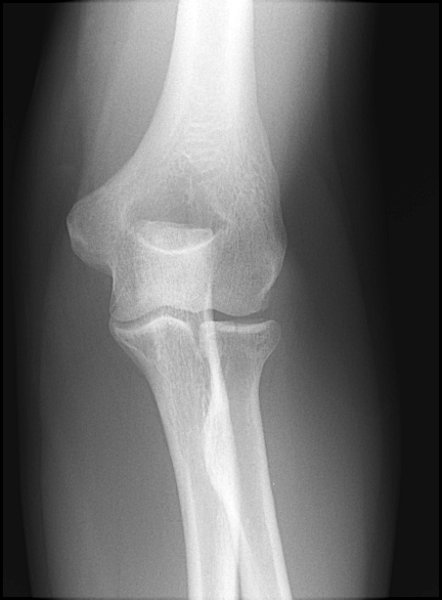

Return to Radial Head Fracture